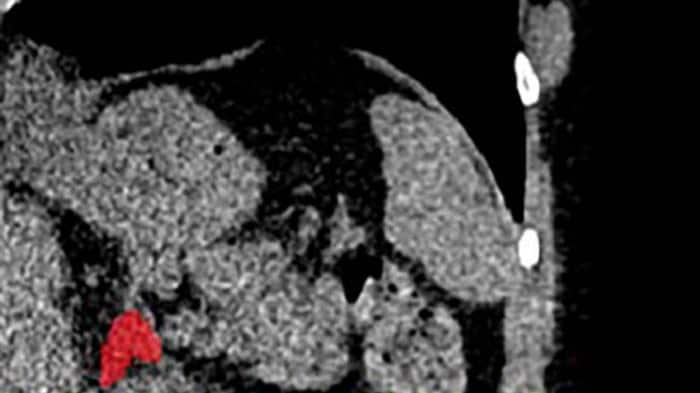

Y es que un equipo de investigadores liderado por la doctora Elena Ghotbi, del Johns Hopkins University School of Medicine, en Estados Unidos, entrenó un modelo de aprendizaje profundo para medir el volumen de las glándulas suprarrenales a partir de tomografías de tórax ya realizadas.

El indicador, llamado Índice de Volumen Suprarrenal (AVI, por sus siglas en inglés), se define como el volumen de las glándulas suprarrenales dividido por la estatura al cuadrado.

Este hallazgo representa una verdadera innovación clínica: por primera vez es posible “ver” el estrés crónico acumulado en el cuerpo mediante una imagen médica habitual, en lugar de depender únicamente de cuestionarios o mediciones puntuales de cortisol.